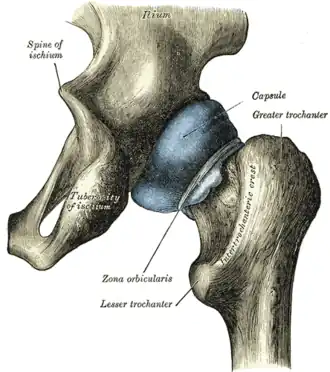

In human anatomy, the lesser trochanter is a conical, posteromedial, bony projection from the shaft of the femur. It serves as the principal insertion site of the iliopsoas muscle.[1]

The lesser trochanter is a conical posteromedial projection of the shaft of the femur, projecting from the posteroinferior aspect of its junction with the femoral neck.[1]

The summit and anterior surface of the lesser trochanter are rough, whereas its posterior surface is smooth.[1]

From its apex three well-marked borders extend:[2]

- two of these are above

- a medial continuous with the lower border of the femur neck

- a lateral with the intertrochanteric crest

- the inferior border is continuous with the middle division of the linea aspera

The summit of the lesser trochanter gives insertion to the tendon of the psoas major muscle and the iliacus muscle;[3] the lesser trochanter represents the principal attachment of the iliopsoas.[1]

The intertrochanteric crest (which demarcates the junction of the femoral shaft and neck posteriorly) extends between the lesser trochanter and the greater trochanter on the posterior surface of the femur.[1]